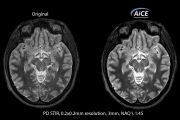

Fejlett intelligens Clear-IQ motor (AiCE)

A tisztaság új korszaka kezdődött

Az AiCE* lenyűgöző MR-képeket készít, amelyek kivételesen részletesek és olyan alacsony zajszintűek, mint amilyet egy nagy SNR-értékű képtől elvárhat.